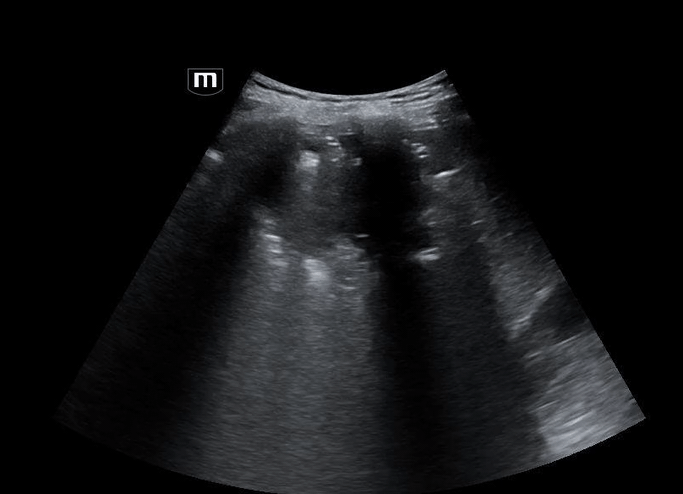

Using the curvilinear probe, we see a well-defined, round lesion within the liver parenchyma on the right lower quadrant US:

Based on the patient’s ultrasound findings, the appearance is consistent with a hepatic abscess.

• Appearance: focal, hypoechoic or complex cystic lesion within liver parenchyma

• Echotexture: heterogeneous, may contain septations, debris, or internal echoes

• Borders: irregular or ill-defined; chronic abscesses may develop capsule

• Gas formation: echogenic foci with dirty shadowing or ring-down artifacts (seen in Klebsiella/E. coli)

• Posterior acoustic enhancement: fluid-filled lesion characteristic

• Color Doppler: peripheral hyperemia, absent central vascularity

• Location: most commonly in the right hepatic lobe due to its greater blood supply and biliary drainage.

• Multiple hepatic abscesses, the largest located in the right hepatic lobe, measuring 13.3 cm